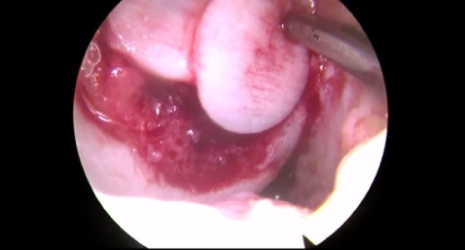

미세천공술

피부에 상처가 나면 스스로 치유되는 이유는 혈액 속 상처를 치유하는 재생인자가 있기 때문입니다. 그러나 연골에는 혈관이 없어 손상되더라도 스스로 치유하는 능력이 없습니다.

미세천공술은 관절내시경 수술을 통해 연골에 3mm 간격으로 4mm 정도의 작은 구멍들을 의도적으로 내어 출혈을 유도하고 골수를 자극하며 연골이 재생될 수 있도록 하는 치료법입니다.

□ 이전부터 시행되고 있는 재생 치료로, ‘섬유성 연골’로 재생

□ 관절내시경을 통해 시행되어 절개가 작고 부담이 적음

□ 출혈이나 부작용이 거의 없으며 조직 손상이 적음

□ 시행 후 회복이 빠르고 통증이 적음